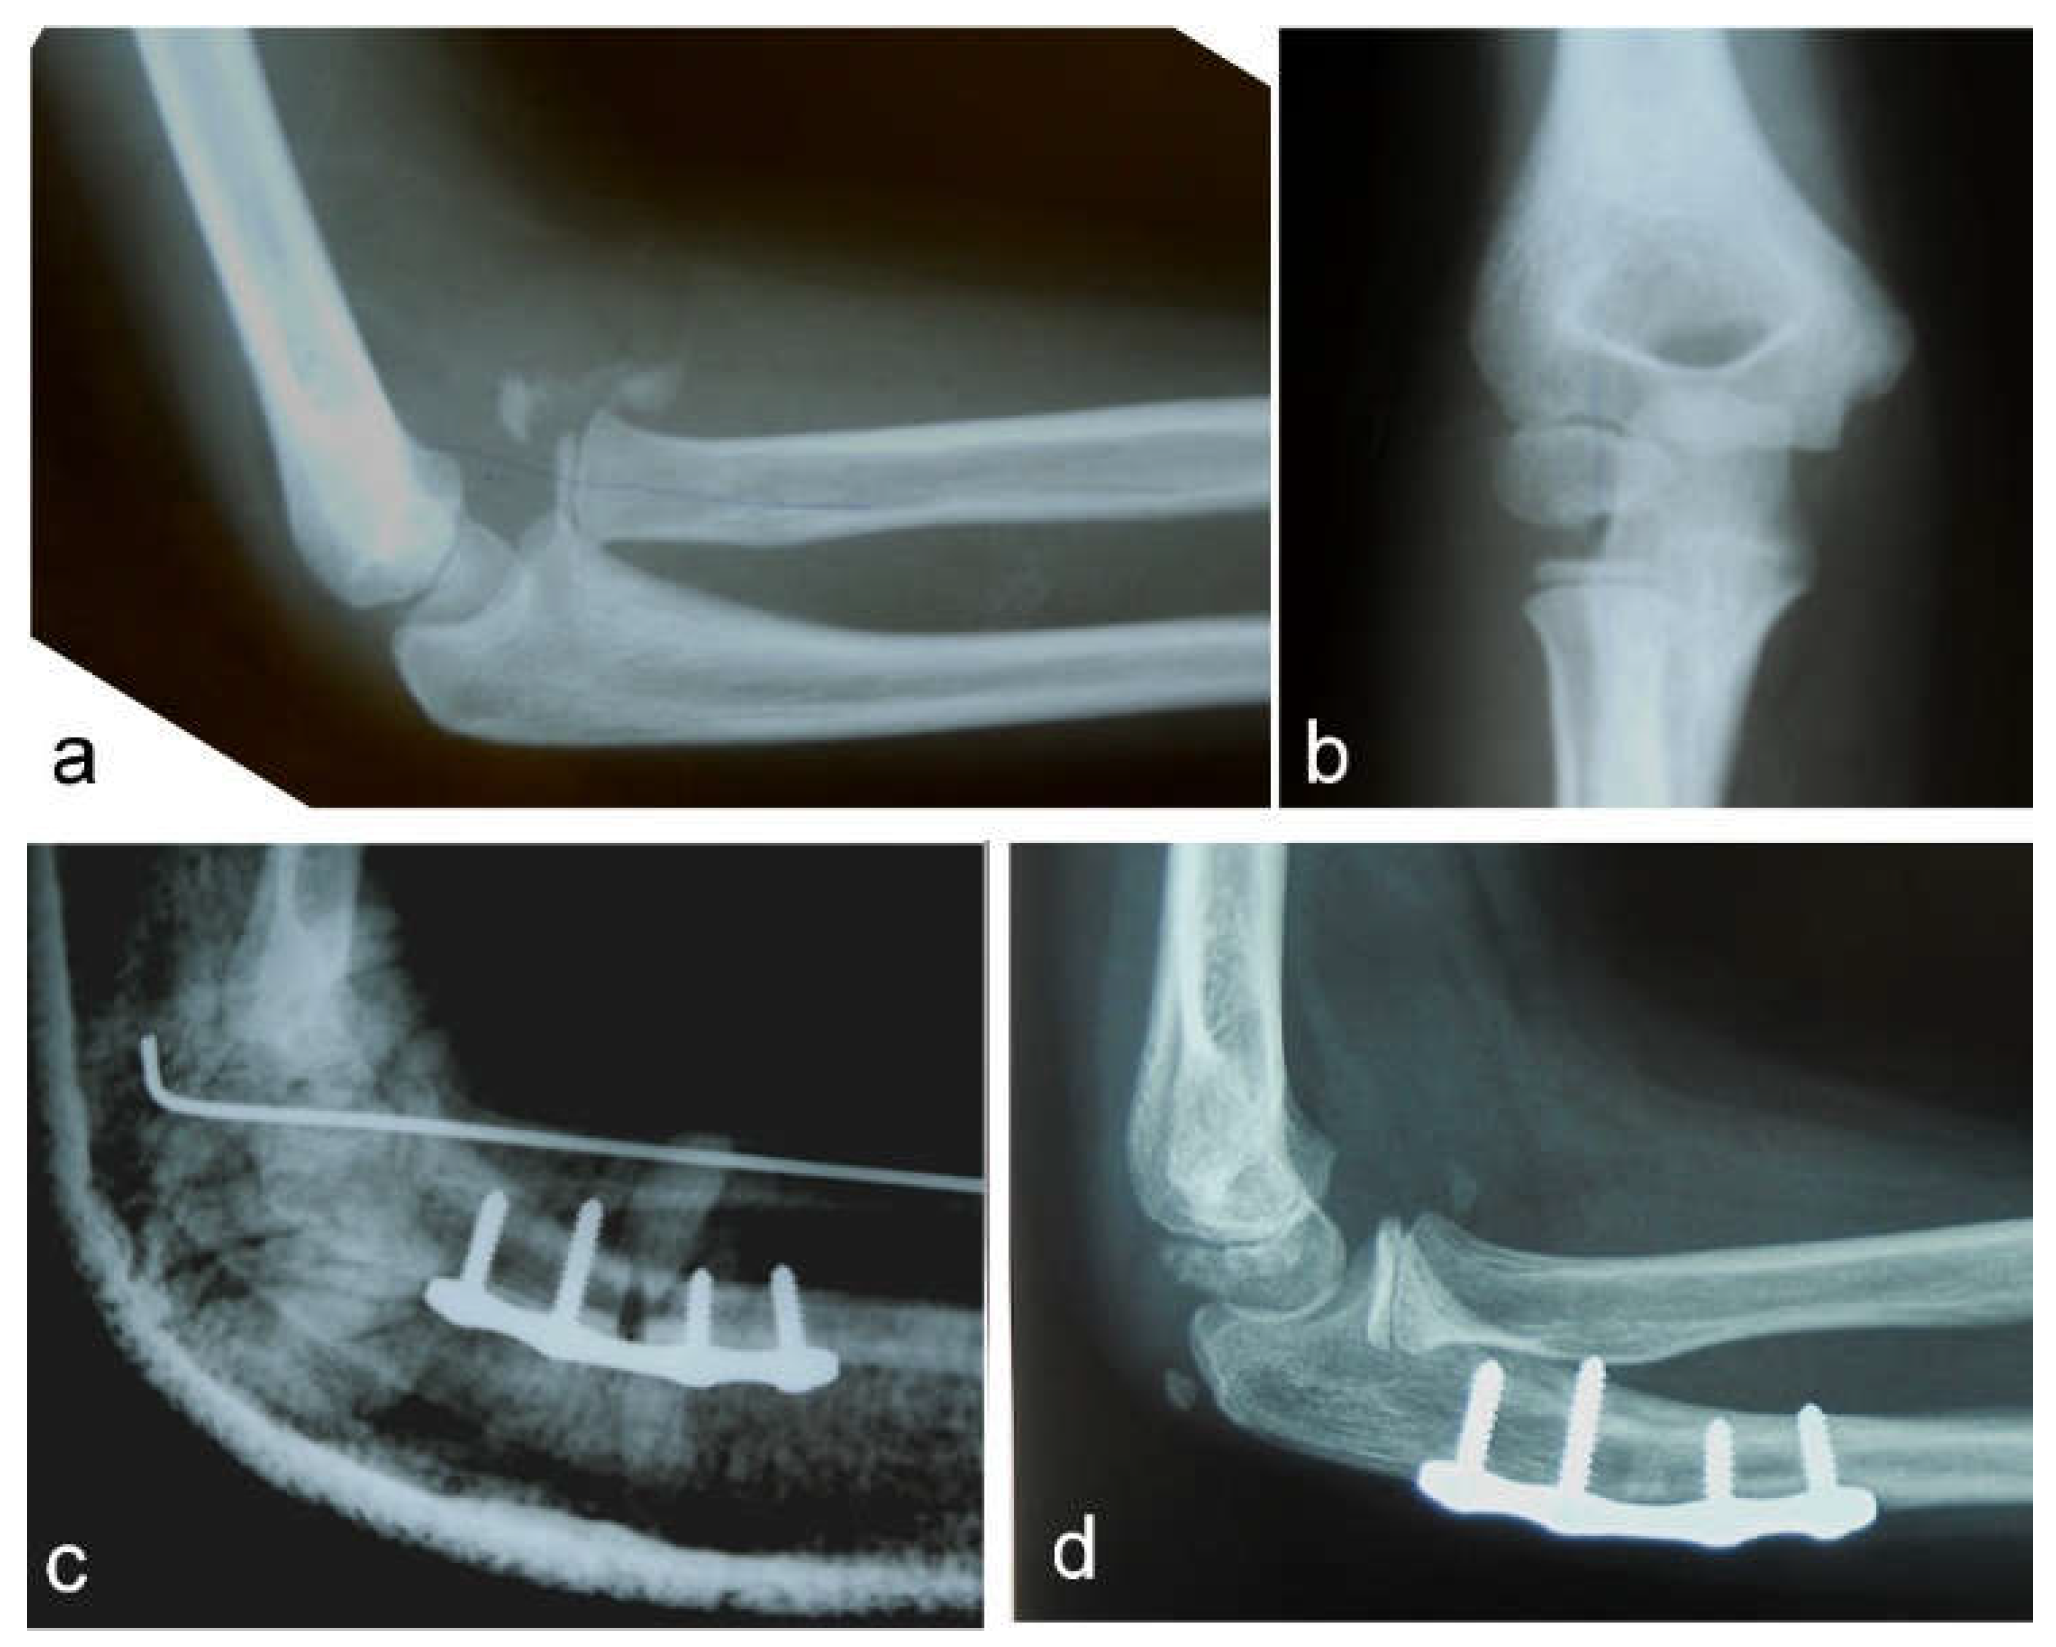

Nine patients had a Bado type I injury, with the radial head displaced anteriorly, and four patients had a Bado type III injury, with lateral and anterior radial head displacement. All patients were treated as soon as possible after a diagnosis of the missed Monteggia fracture was established. The period from diagnosis to surgery varied from 2 days to 2 weeks. An autologous bone graft, harvested from the iliac crest, was used in only one case to fill the gap after osteotomy of the ulna. Another nine osteotomies of the ulna and three osteotomies of the radius healed without bone grafting. All osteotomies of the ulna and two osteotomies of the radius were stabilized with plates and 4–8 screws (Figure 1 and Figure 2).

All the patients in our study were operated on shortly after being diagnosed with a chronic Monteggia lesion. However, there is no need to hurry. Thorough preoperative planning of the reconstructive procedure is very important. A set of correct radiographs in true AP and lateral projection of both injured and uninjured forearms should be obtained [9]. If any discrepancy in the physiological curve of the ulna exists, it should be corrected by ulnar osteotomy. Straightening the natural ulnar curve may result in an incomplete reduction of the radial head, re-dislocation or even late dislocation [24]. We observed re-dislocation of a reduced radial head in one patient as the cause of their chronic Monteggia lesion. His ulna fracture was originally stabilized with a retrograde elastic titanium nail, but progressive loss of reduction with angulation of the ulna occurred. That was left unnoticed until the follow-up for cast removal, which was 4 weeks after the surgery. Revision and fixation with a plate and screws were subsequently performed. We believe that retrograde ESIN may provide insufficient stabilization of the ulnar fracture in a Monteggia injury. Anterograde ESIN through the olecranon entry point may be a better solution. Alternatively, open reduction and plating of the ulna may be performed. If malalignment of the ulna exists, then an osteotomy of the ulna should be the first step in the treatment of chronic Monteggia fractures, especially 3–4 months from the initial injury. A posterior angulation and elongation osteotomy of the ulna, as described by Bouyala [25], is currently the preferred method. Performing an osteotomy high in the metaphyseal region of the proximal third of the ulna may decrease the risk of delayed union or nonunion. Eight of our patients were treated this way (Figure 1). Other authors prefer a more distal osteotomy at the site of maximal angulation of the ulna [26]. Sliding [2] and “Z”-lengthening [27] osteotomies of the ulna have been recently published. In two of our patients, correction of ulnar angulation was performed at the level of a fracture of the ulna. Both patients underwent surgery 5 weeks after their injury, and their fractures, although consolidated, were not completely healed; we decided to correct the deformity at that level (Figure 2). Kim et al. [28] recently performed a 3-dimensional analysis of the deformation of the ulna in patients with chronic radial head dislocation. They found not only angulation but a complex torsional deformity of the ulna. This may explain why a simple angulation-lengthening osteotomy of the ulna may not be completely effective in all cases, especially in Bado type III cases, as reported by Delpont et al. [14] and was observed in one of our cases. Correction of such a complex deformity requires complex correction in two or three planes.

Figure 1. Neglected Monteggia fracture: (a) anterior dislocation of the radial head with heterotopic ossification visible on a lateral view; (b) AP view; (c) high posterior angulation and elongation osteotomy of the ulna stabilized with a plate and four screws. Transcapitellar fixation of the radial head with Kirschner wire; (d) the reduced radial head and healed ulnar osteotomy are visible on a lateral X-ray before removal of the plate and screws.